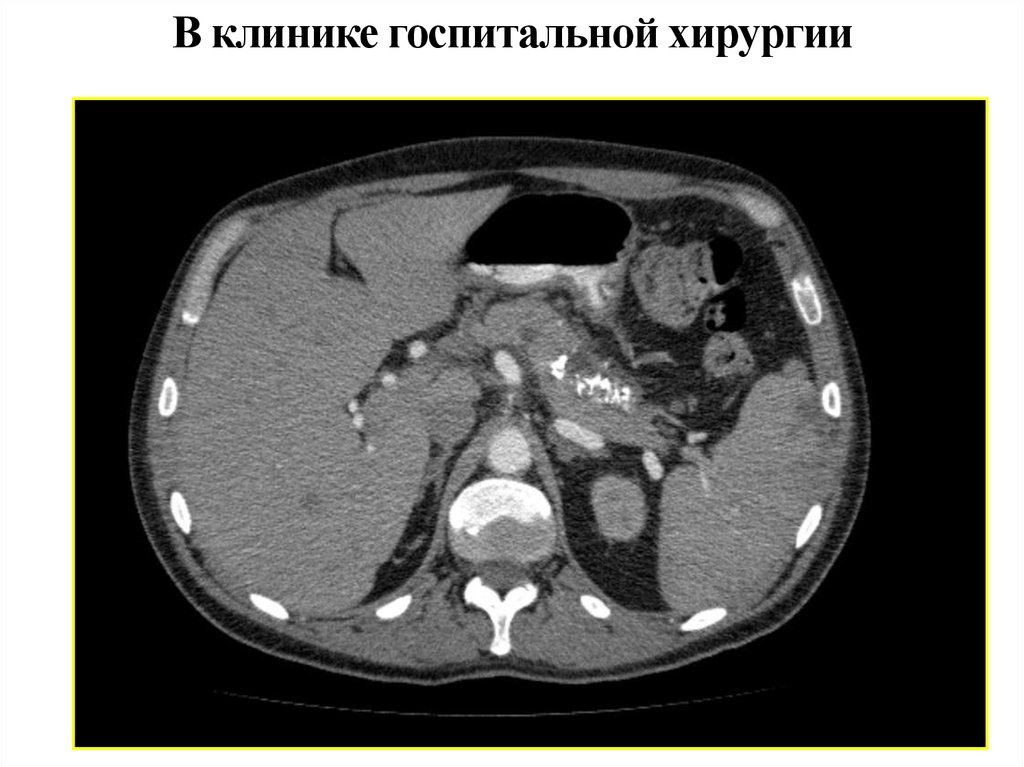

82. В клинике госпитальной хирургии

ФЭГДС в день поступления

В желудке большое количество содержимого по типу «кофейной гущи». После отмывания слизистая оболочка желудка во

всех отделах отечная, бледная. Слизистая

оболочка луковицы двенадцатиперстной

кишки с единичными острыми эрозиями

0,2 см под фибрином. В залуковичном

отделе отмечается поступление темной

желчи. В субкардиальном отделе определяются варикозно расширенные вены.

Источник кровотечения не обнаружен

В клинике госпитальной хирургии

12.01.11 - компьютерная томография

На границе тела и хвоста поджелудочной железы выявлено образование жидкостной плотности 15х19 мм

с обызвествлением по контуру, без

явного накопления контраста.

Структура хвоста неоднородная, с

множественными кальцинатами,

панкреатический проток не расширен.